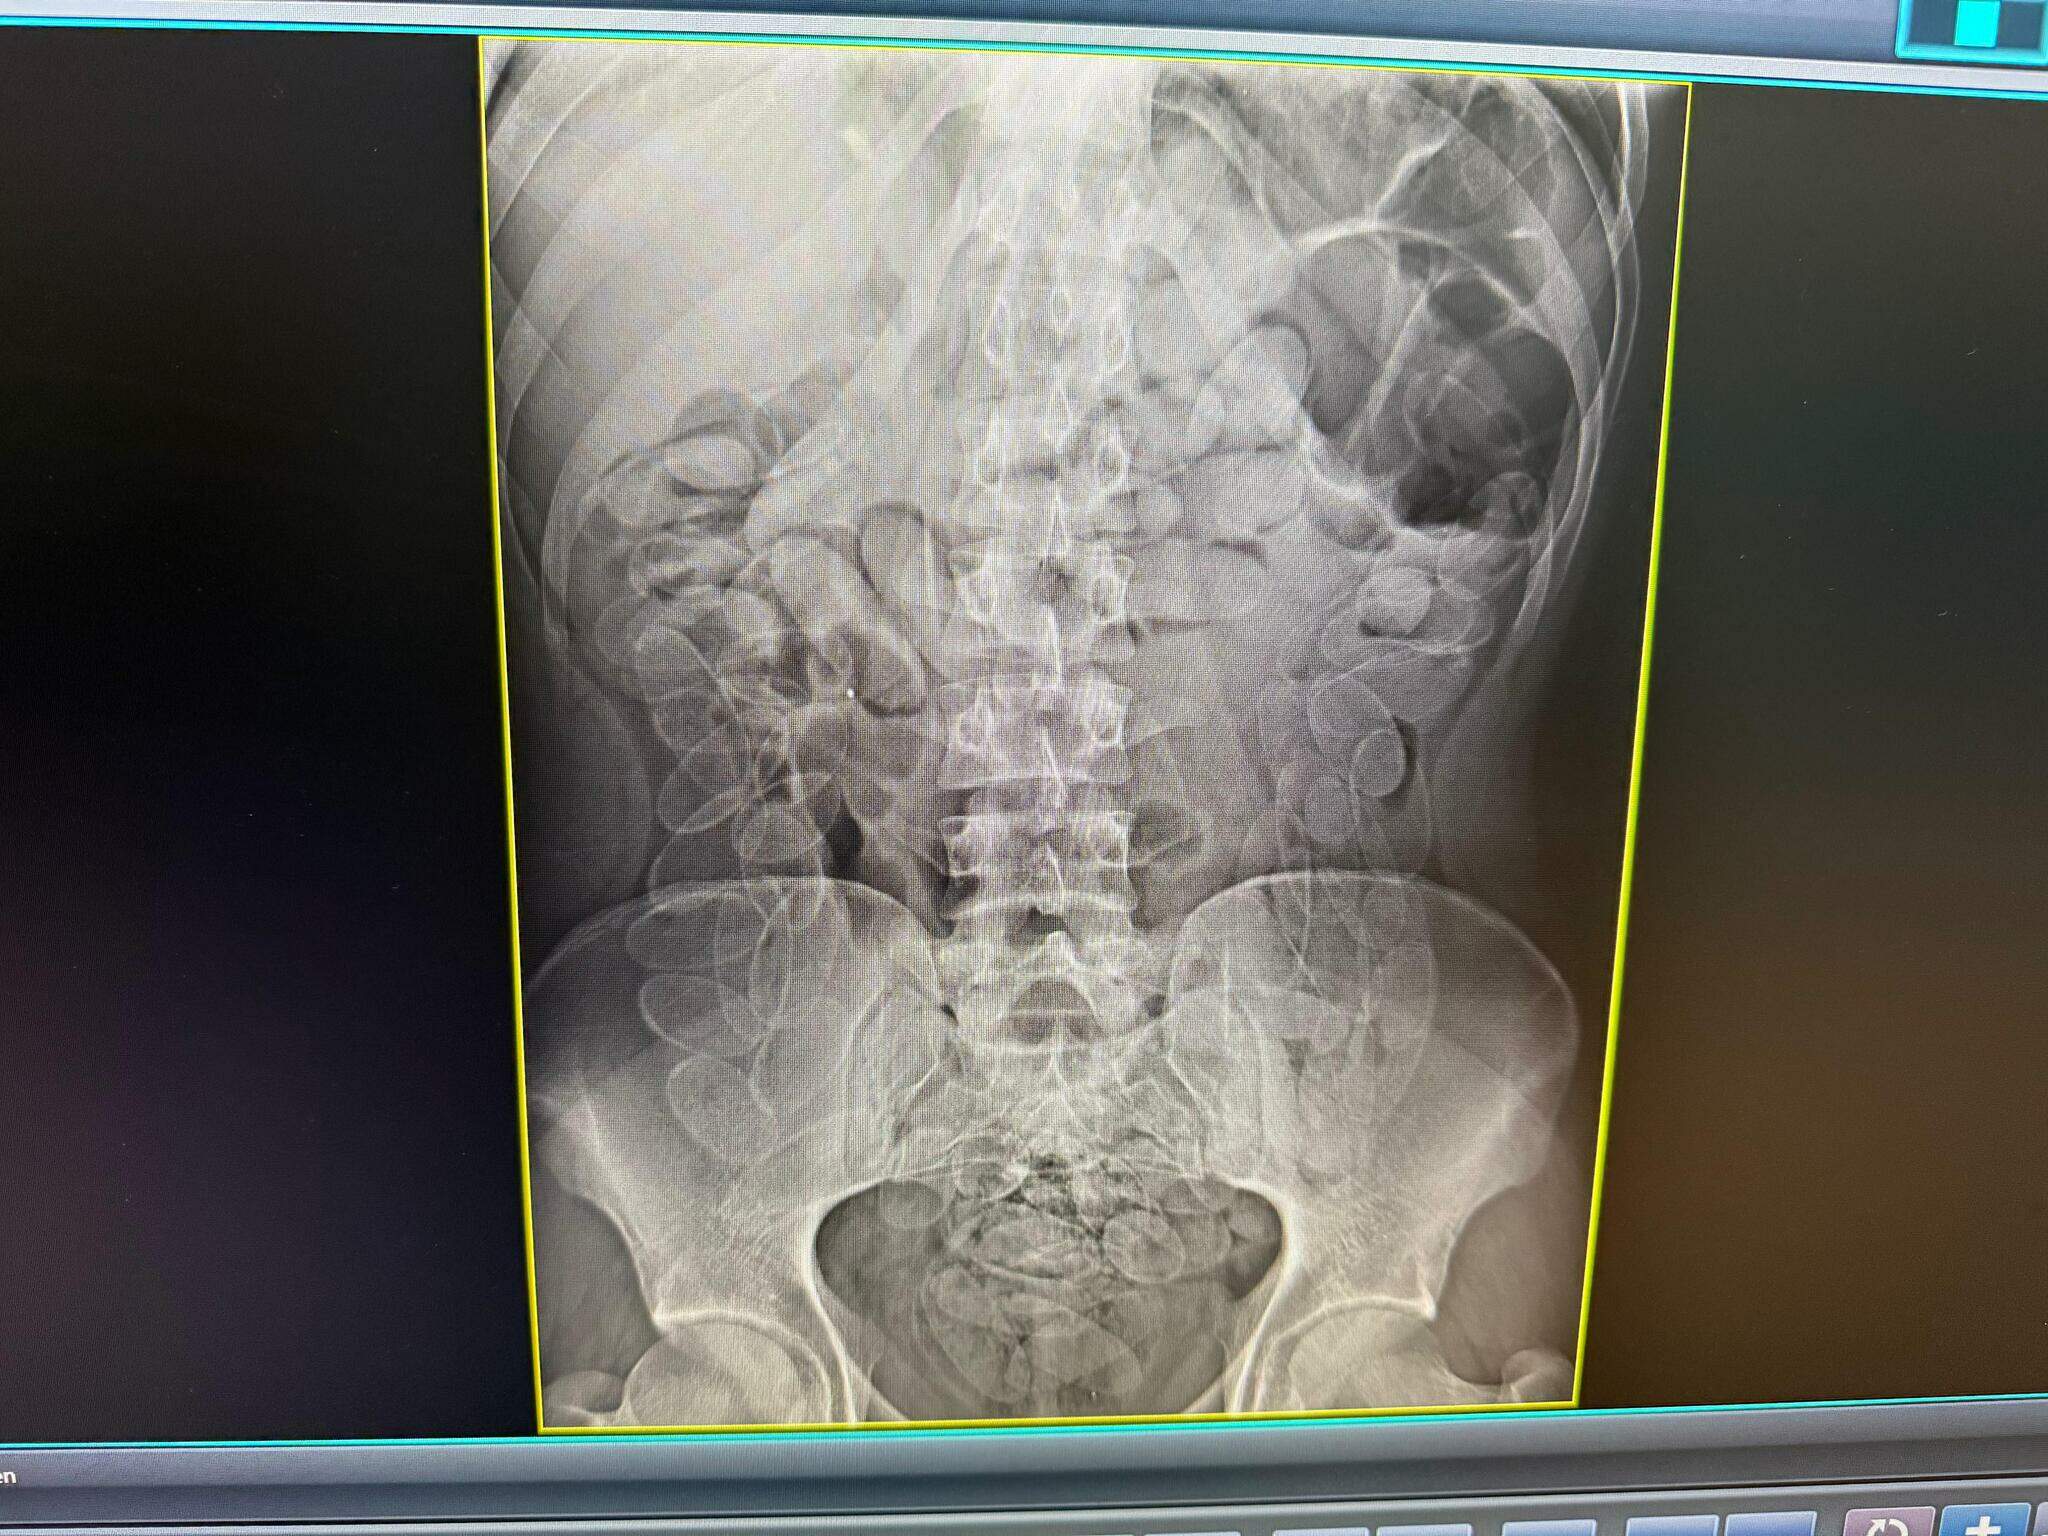

Rapaz de 24 anos, de nacionalidade boliviana, foi preso após ingerir 90 cápsulas de cocaína durante abordagem no Posto de Fiscalização Esdras, em Corumbá, distante 428 quilômetros de Campo Grande, no último fim de semana, durante ação realizada em conjunto pela Receita Federal, pelo Mapa (Ministério da Agricultura, Pecuária e Abastecimento) e pela Polícia Militar.

As equipes faziam fiscalizações na região do Posto Esdras quando abordaram um táxi que entrava no país; o passageiro apresentou nervosismo excessivo e contou que havia ingerido as cápsulas de droga. Ele foi encaminhado à Santa Casa de Corumbá, onde permaneceu sob acompanhamento médico até a expulsão segura do material.